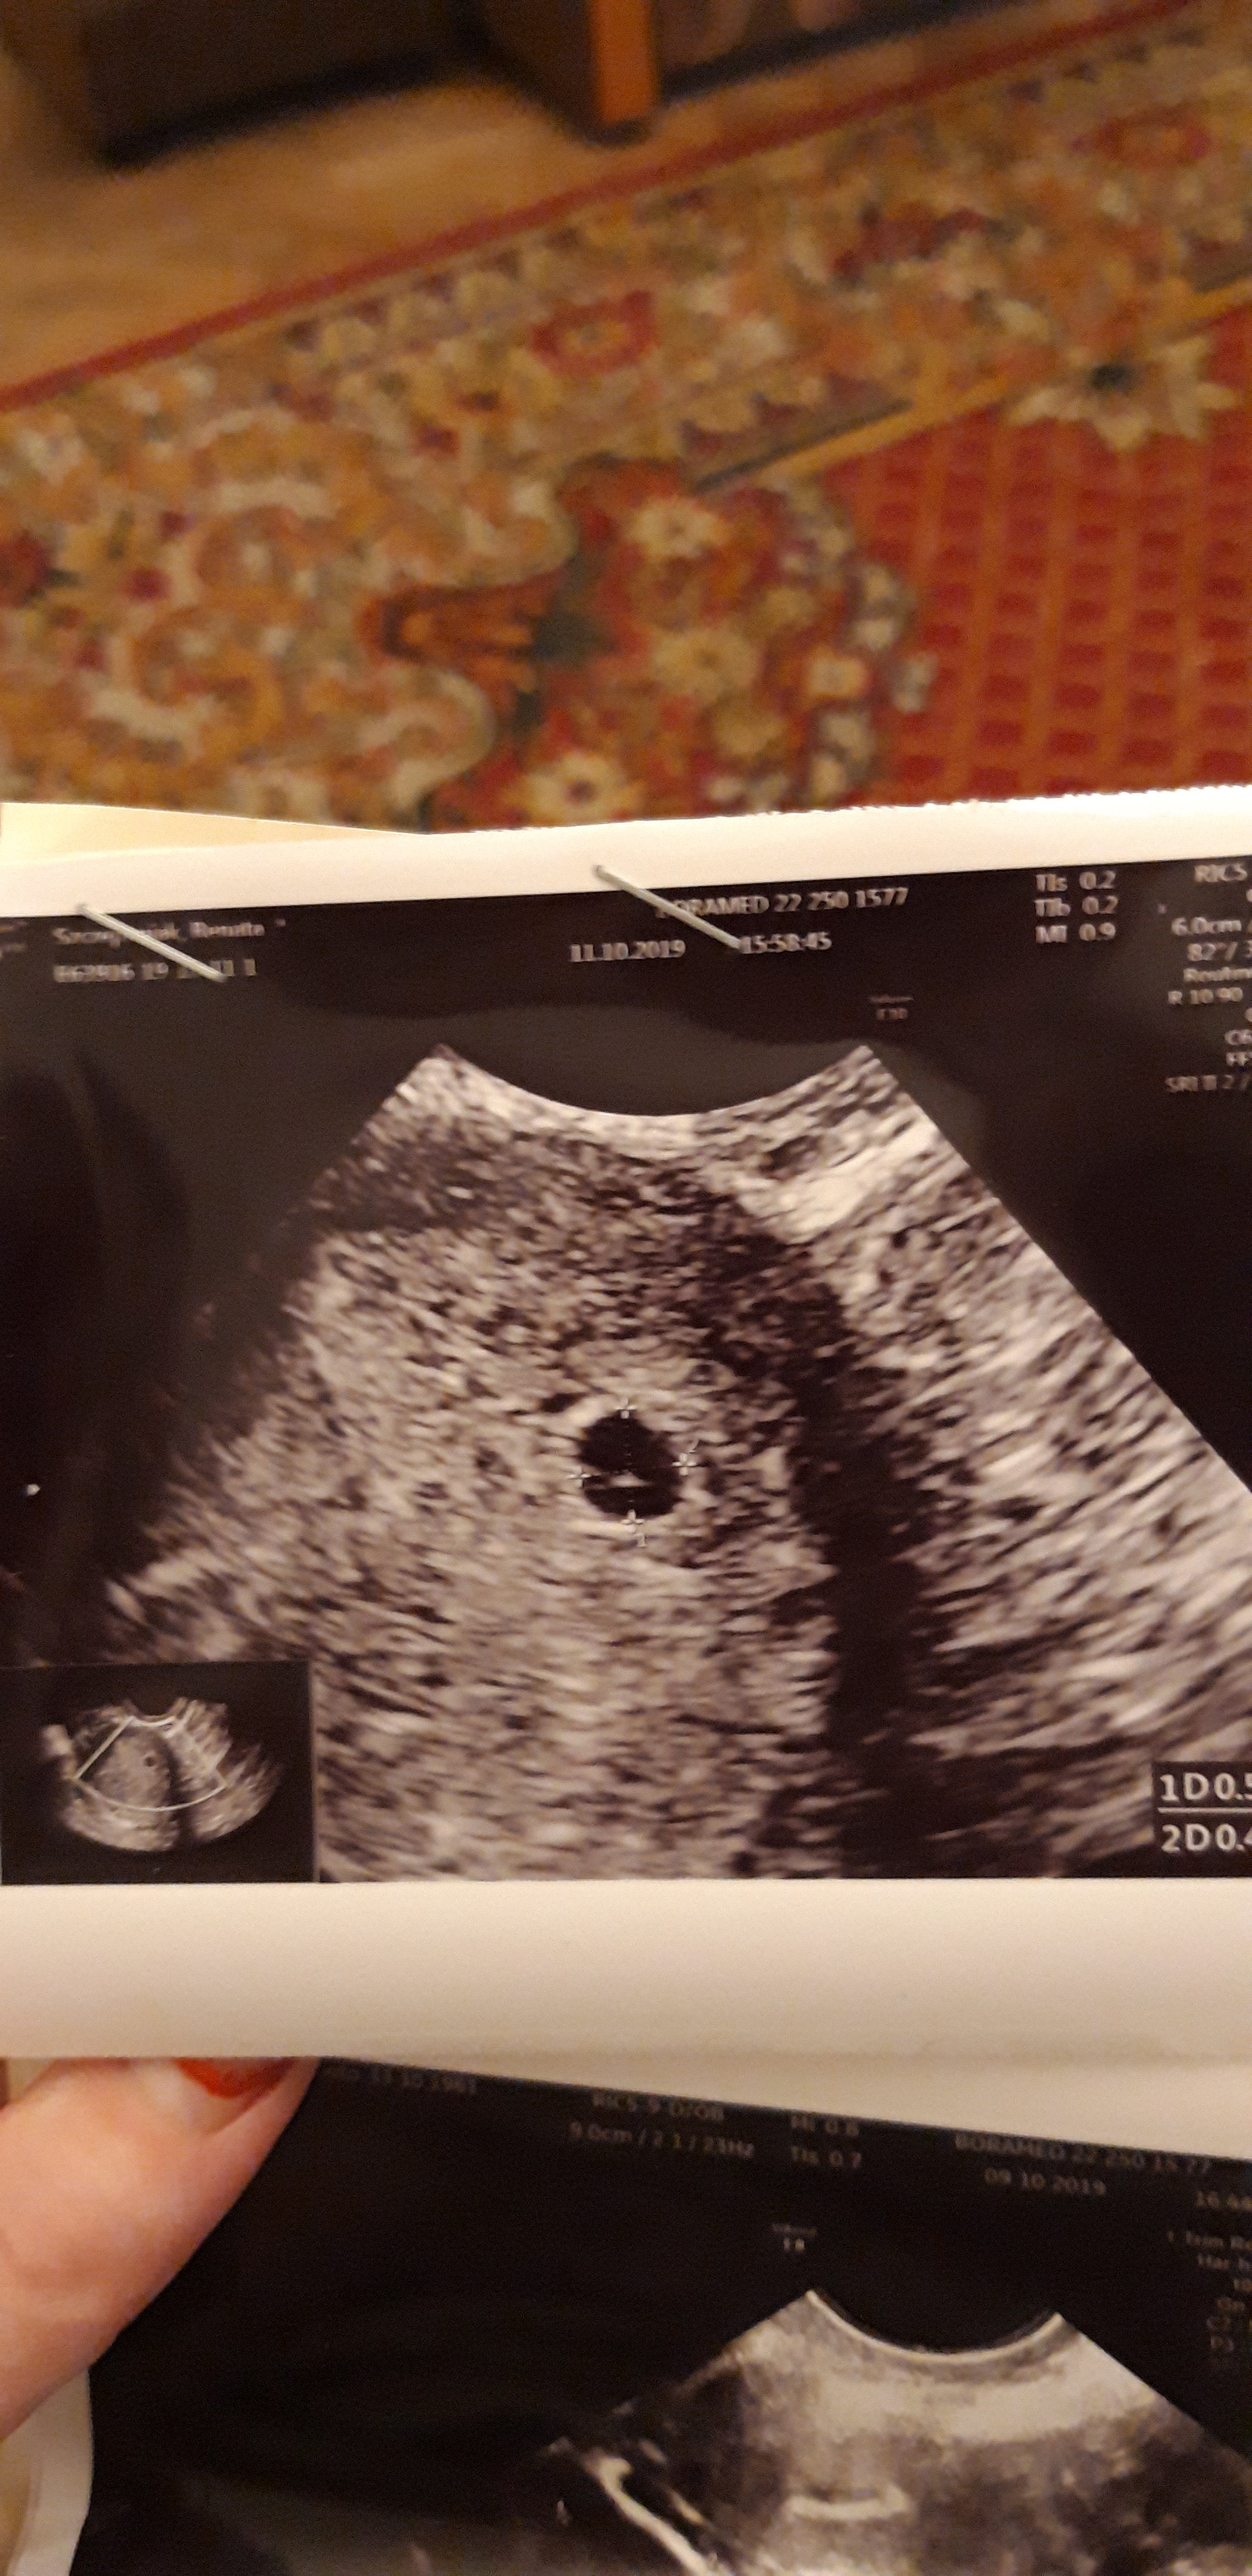

czy to ciaza

dostalam skierowanie n.a. patologie ciazy ale on ppwiedzial ze nie wiem dokładnie czy to ciaza

Z tego zdjęcia ciężko wywnioskować czy to rzeczywiście ciąża. W 8 tygodniu widać ja wyraźnie na usg. Skoro lekarz ma wątpliwości to czy my jesteśmy na tyle kompetentne aby Ci odpowiedzieć? Nie masz możliwości pójść do innego lekarza z lepszym sprzętem?

I to brzmi rozsądnie. Może nie chciał Cię straszyć na zapas swoimi podejrzeniami ani naciągać na platne badania i uznał, że lepiej, żeby w szpitalu się Tobą zajęto. Zapisz sobie kiedy ostatnio miałaś miesiączkę, bo ginekolodzy nie pytają o datę owulacji, tylko ostatniej miesiączki i o to ile trwają Twoje cykle.